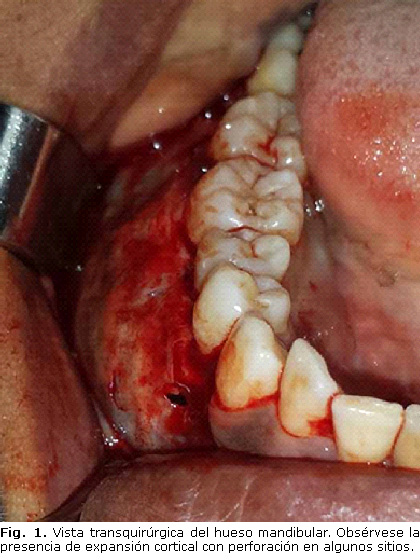

Se decide realizar abordaje quirúrgico intrabucal del área bajo anestesia local lográndose la exposición amplia de la zona y confirmándose la presencia de expansión cortical (Fig. 1).